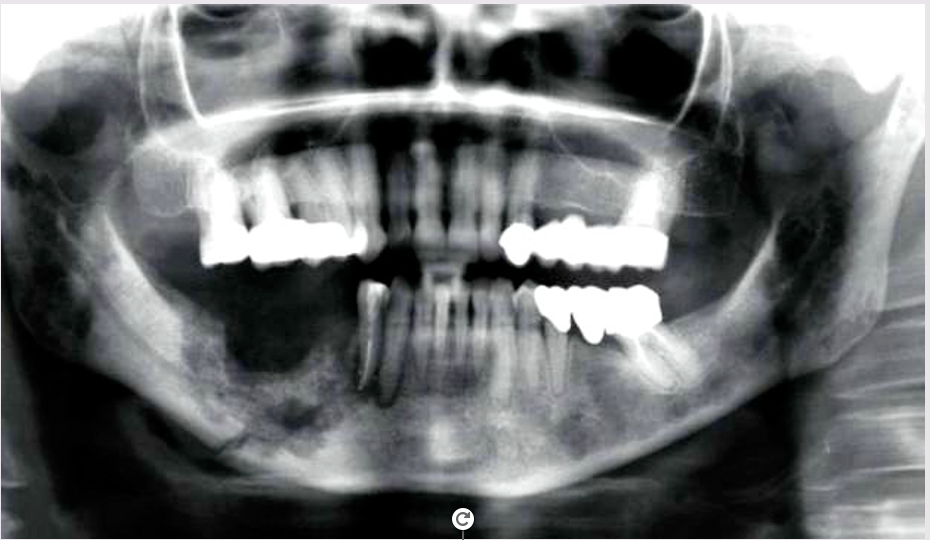

What is stage 3 MRONJ?

What is the treatment?

A

Symptomatic exposed bone and infection.

Pathological fracture, presence of a fistula or signs of osteolysis.

Analgesics and antibiotics

Antiseptic mouthwash

Surgical debridement or resection for long term care